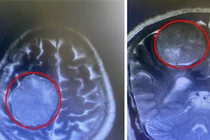

Các giáo sư đầu ngành về phẫu thuật thần kinh Bệnh viện Việt Đức đã cùng các bác sĩ Bệnh viện Việt Nam – Thụy Điển Uông bí đã lấy thành công khối u não kích thước 4,7x5,6cm trong não bệnh nhân 66 tuổi.